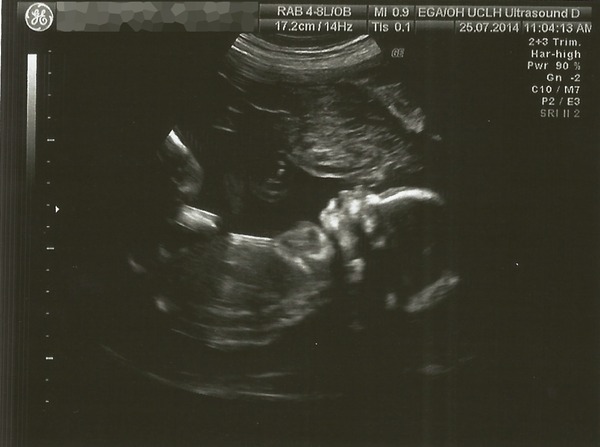

The pic is not very clear but here we go, meet baby Juliette. Scan results are all good, we worried a bit as they spent a lot of time on the heart because they had trouble seeing what they were looking for. Baby was shy and hiding her face with her arms and sucking her thumb. Lots of poking from the sonographer didn't make her change her mind/position, little stubborn thing Grin

Her bedroom will NOT be pink but that evens out the score. 2-2